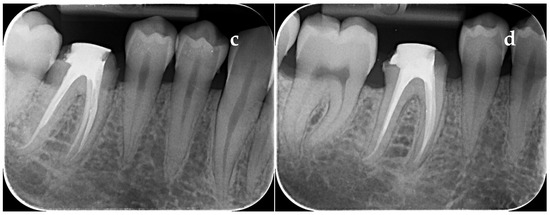

3.2. Paraclinical Evaluation

3.2.1. Evaluation of the PAI Score on Group with Dehydrated Plant Extract

3.2.2. Evaluation of the PAI Score on Group with Calcium Hydroxide

3.2.3. Evaluation of the PAI Score on Group with Calcium Hydroxide Mixed with CHX Gel 2%

3.2.4. Evaluation of the PAI Score on Group with Walkhoff Paste